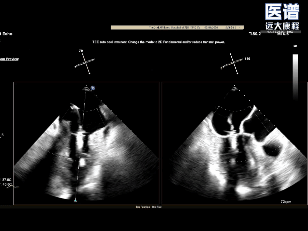

TEE

TEE-2D血流

术前超声

重度DMR,LVEF 61%,LVIDd 5.62cm,LVIDs 3.27cm,VCW 0.72cm,EROA=0.47cm2;RV=83ml,PG mean 3mmHg,PASP 51mmHg。

病变位置为:A1邻近交界处脱垂;宽度/高度:1.08cm/0.29cm;A1/P1瓣叶长度:1.38cm/1.17cm;前后径(AP直径):3.56cm;二尖瓣口面积:4.39cm2